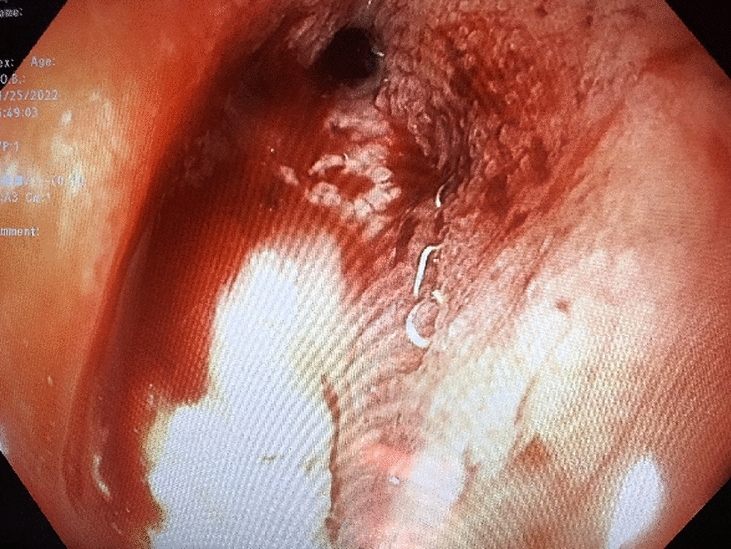

M. Carolina Jimenez, MD; Robert F. Cubas, MD; Jose M. Martinez, MD; University of Miami/Jackson Health System

Introduction: Biologic mesh has been used in clean-contaminated and contaminated fields and while wound infection rates may be high, infection is usually superficial and graft removal is unusual. Biologic mesh has been reported to have higher recurrence rates and poor incorporation into native tissue in comparison to synthetic mesh. Currently, there is no consensus on mesh preservation treatment in cases of mesh infection after hernia repair.

Methods: We present a 72-year-old male with prior radical cystectomy and neobladder creation complicated at the time by neobladder-cutaneous fistula and wound infection requiring revisional surgery and incisional hernia repair with mesh. He developed a large recurrent incisional hernia and underwent open hernia repair with bilateral anterior component separation, extensive lysis of adhesions, removal of prior mesh, and placement of a biologic mesh (Strattice™ RTM) in an underlay and onlay fashion. Intraoperatively, the defect measured 20 cm long by 14 cm wide. Postoperatively, he was treated for neobladder infection and CT cystogram found no extravasation from the neobladder. He presented to the emergency department 6 weeks after surgery with spontaneous partial midline wound dehiscence, with exposure of the onlay mesh and drainage of clear fluid, which was confirmed to be urine by fluid creatinine level. Repeat CT scan demonstrated a filling defect at the anterior wall of the neobladder with contrast leaking into a contained collection interposed between the anterior abdominal wall and the underlay mesh, extending superiorly between the small bowel loops and dehiscence of the midline abdominal wound. The patient was treated with a course of antibiotics and indwelling Foley catheter and bilateral nephrostomy tubes for urine diversion.

Results: Three months later, repeat CT cystogram demonstrated resolution of the leak and the nephrostomy tubes and Foley catheter were removed. The patient has continued daily wound care with significant reduction in size of the midline wound and increasing granulation tissue around the onlay mesh. He has not required further admissions to hospital and there has been no hernia recurrence so far.

Conclusion: In the appropriate setting, contaminated biologic mesh after surgery may be treated with medical management with adequate wound closure, avoiding the need for surgery and mesh explantation.